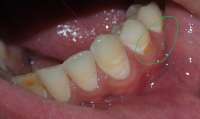

14730060113960.jpg (1696Кб, 3584x2016)

14730060114311.jpg (1712Кб, 3584x2016)

14730060114662.jpg (1558Кб, 3584x2016)

>>511739 (OP)

Мои зубки. Запломбировал все дырки коих было много, но внешний вид всё равно оставлял желать лучшего, на последнем приёме у стоматолога спросил насчет отбеливания зубов, какие есть варианты и т.д. она мне ответила, что у меня и так фиговая эмаль и мне нельзя делать отбеливание, дальнейшие расспросы особых результатов не дали. Собственно вопрос - и вправду нет адекватного способа отбелить зубы без вреда для самих зубов? Не очень то хочется бегать желторотиком всю жизнь. И какие еще могут быть способы привести зубы в более привлекательный вид?

Аноним 04/09/16 Вск 19:30:11  513117

>>513114

Виниры\коронки.

Аноним 04/09/16 Вск 19:45:42  513122

>И какие ещё могут быть способы привести зубы в более привлекательный вид?

Нормальные зубы в смысле цвета, чё.

На чистке зубов был? Что то у тебя между зубов какие то отложения. Или это еда?